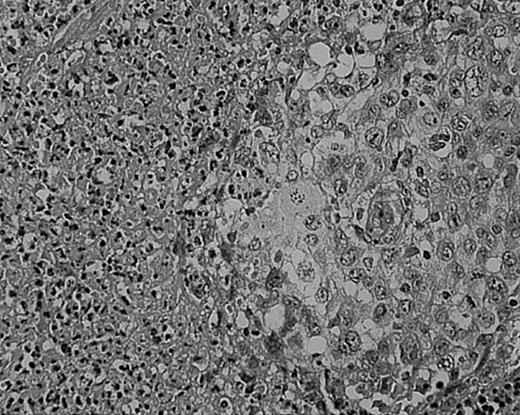

Lymphocyte depletion in NS HD.

This example shows lymphocytes in less than 33% of all cells. Stained with H&E. Original magnification, × 400.